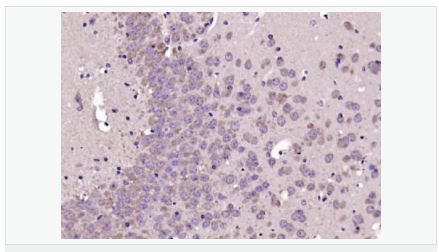

| 產(chǎn)品應(yīng)用 | ELISA=1:5000-10000 IHC-P=1:100-500 IHC-F=1:100-500 IF=1:200-800 (石蠟切片需做抗原修復(fù)) not yet tested in other applications. optimal dilutions/concentrations should be determined by the end user. |

| 產(chǎn)品介紹 | This gene encodes a member of the corticotropin-releasing factor family. The encoded preproprotein is proteolytically processed to generate the mature neuropeptide hormone. In response to stress, this hormone is secreted by the paraventricular nucleus (PVN) of the hypothalamus, binds to corticotropin releasing hormone receptors and stimulates the release of adrenocorticotropic hormone from the pituitary gland. Marked reduction in this protein has been observed in association with Alzheimer's disease. Autosomal recessive hypothalamic corticotropin deficiency has multiple and potentially fatal metabolic consequences including hypoglycemia and hepatitis. In addition to production in the hypothalamus, this protein is also synthesized in peripheral tissues, such as T lymphocytes, and is highly expressed in the placenta. In the placenta it is a marker that determines the length of gestation and the timing of parturition and delivery. A rapid increase in circulating levels of the hormone occurs at the onset of parturition, suggesting that, in addition to its metabolic functions, this protein may act as a trigger for parturition. [provided by RefSeq, Nov 2015] Function: This hormone from hypothalamus regulates the release of corticotropin from pituitary gland. Subunit: Interacts (via C-terminus) with CRFR1 (via N-terminal extracellular domain). Subcellular Location: Secreted. Similarity: Belongs to the sauvagine/corticotropin-releasing factor/urotensin I family. SWISS: P06850 Gene ID: 1392 Database links: Entrez Gene: 1392 Human Entrez Gene: 12918 Mouse Omim: 122560 Human SwissProt: P06850 Human SwissProt: Q8CIT0 Mouse Unigene: 75294 Human Unigene: 290689 Mouse Unigene: 10349 Rat Important Note: This product as supplied is intended for research use only, not for use in human, therapeutic or diagnostic applications. CRF陽性神經(jīng)元的胞體廣泛分布于下丘腦的室旁核、背縫核和藍斑核,這些區(qū)域也是去甲腎上腺素(NE)神經(jīng)元與5-羥色胺(5-HT)神經(jīng)元密集的區(qū)域。 CRF既具有神經(jīng)遞質(zhì)的性質(zhì)又具有神經(jīng)激素的性質(zhì)。CRF是聯(lián)系神經(jīng)系統(tǒng)與內(nèi)分泌系統(tǒng)的橋梁,在情感障礙疾患如焦慮和抑郁的發(fā)病中發(fā)揮重要作用. |